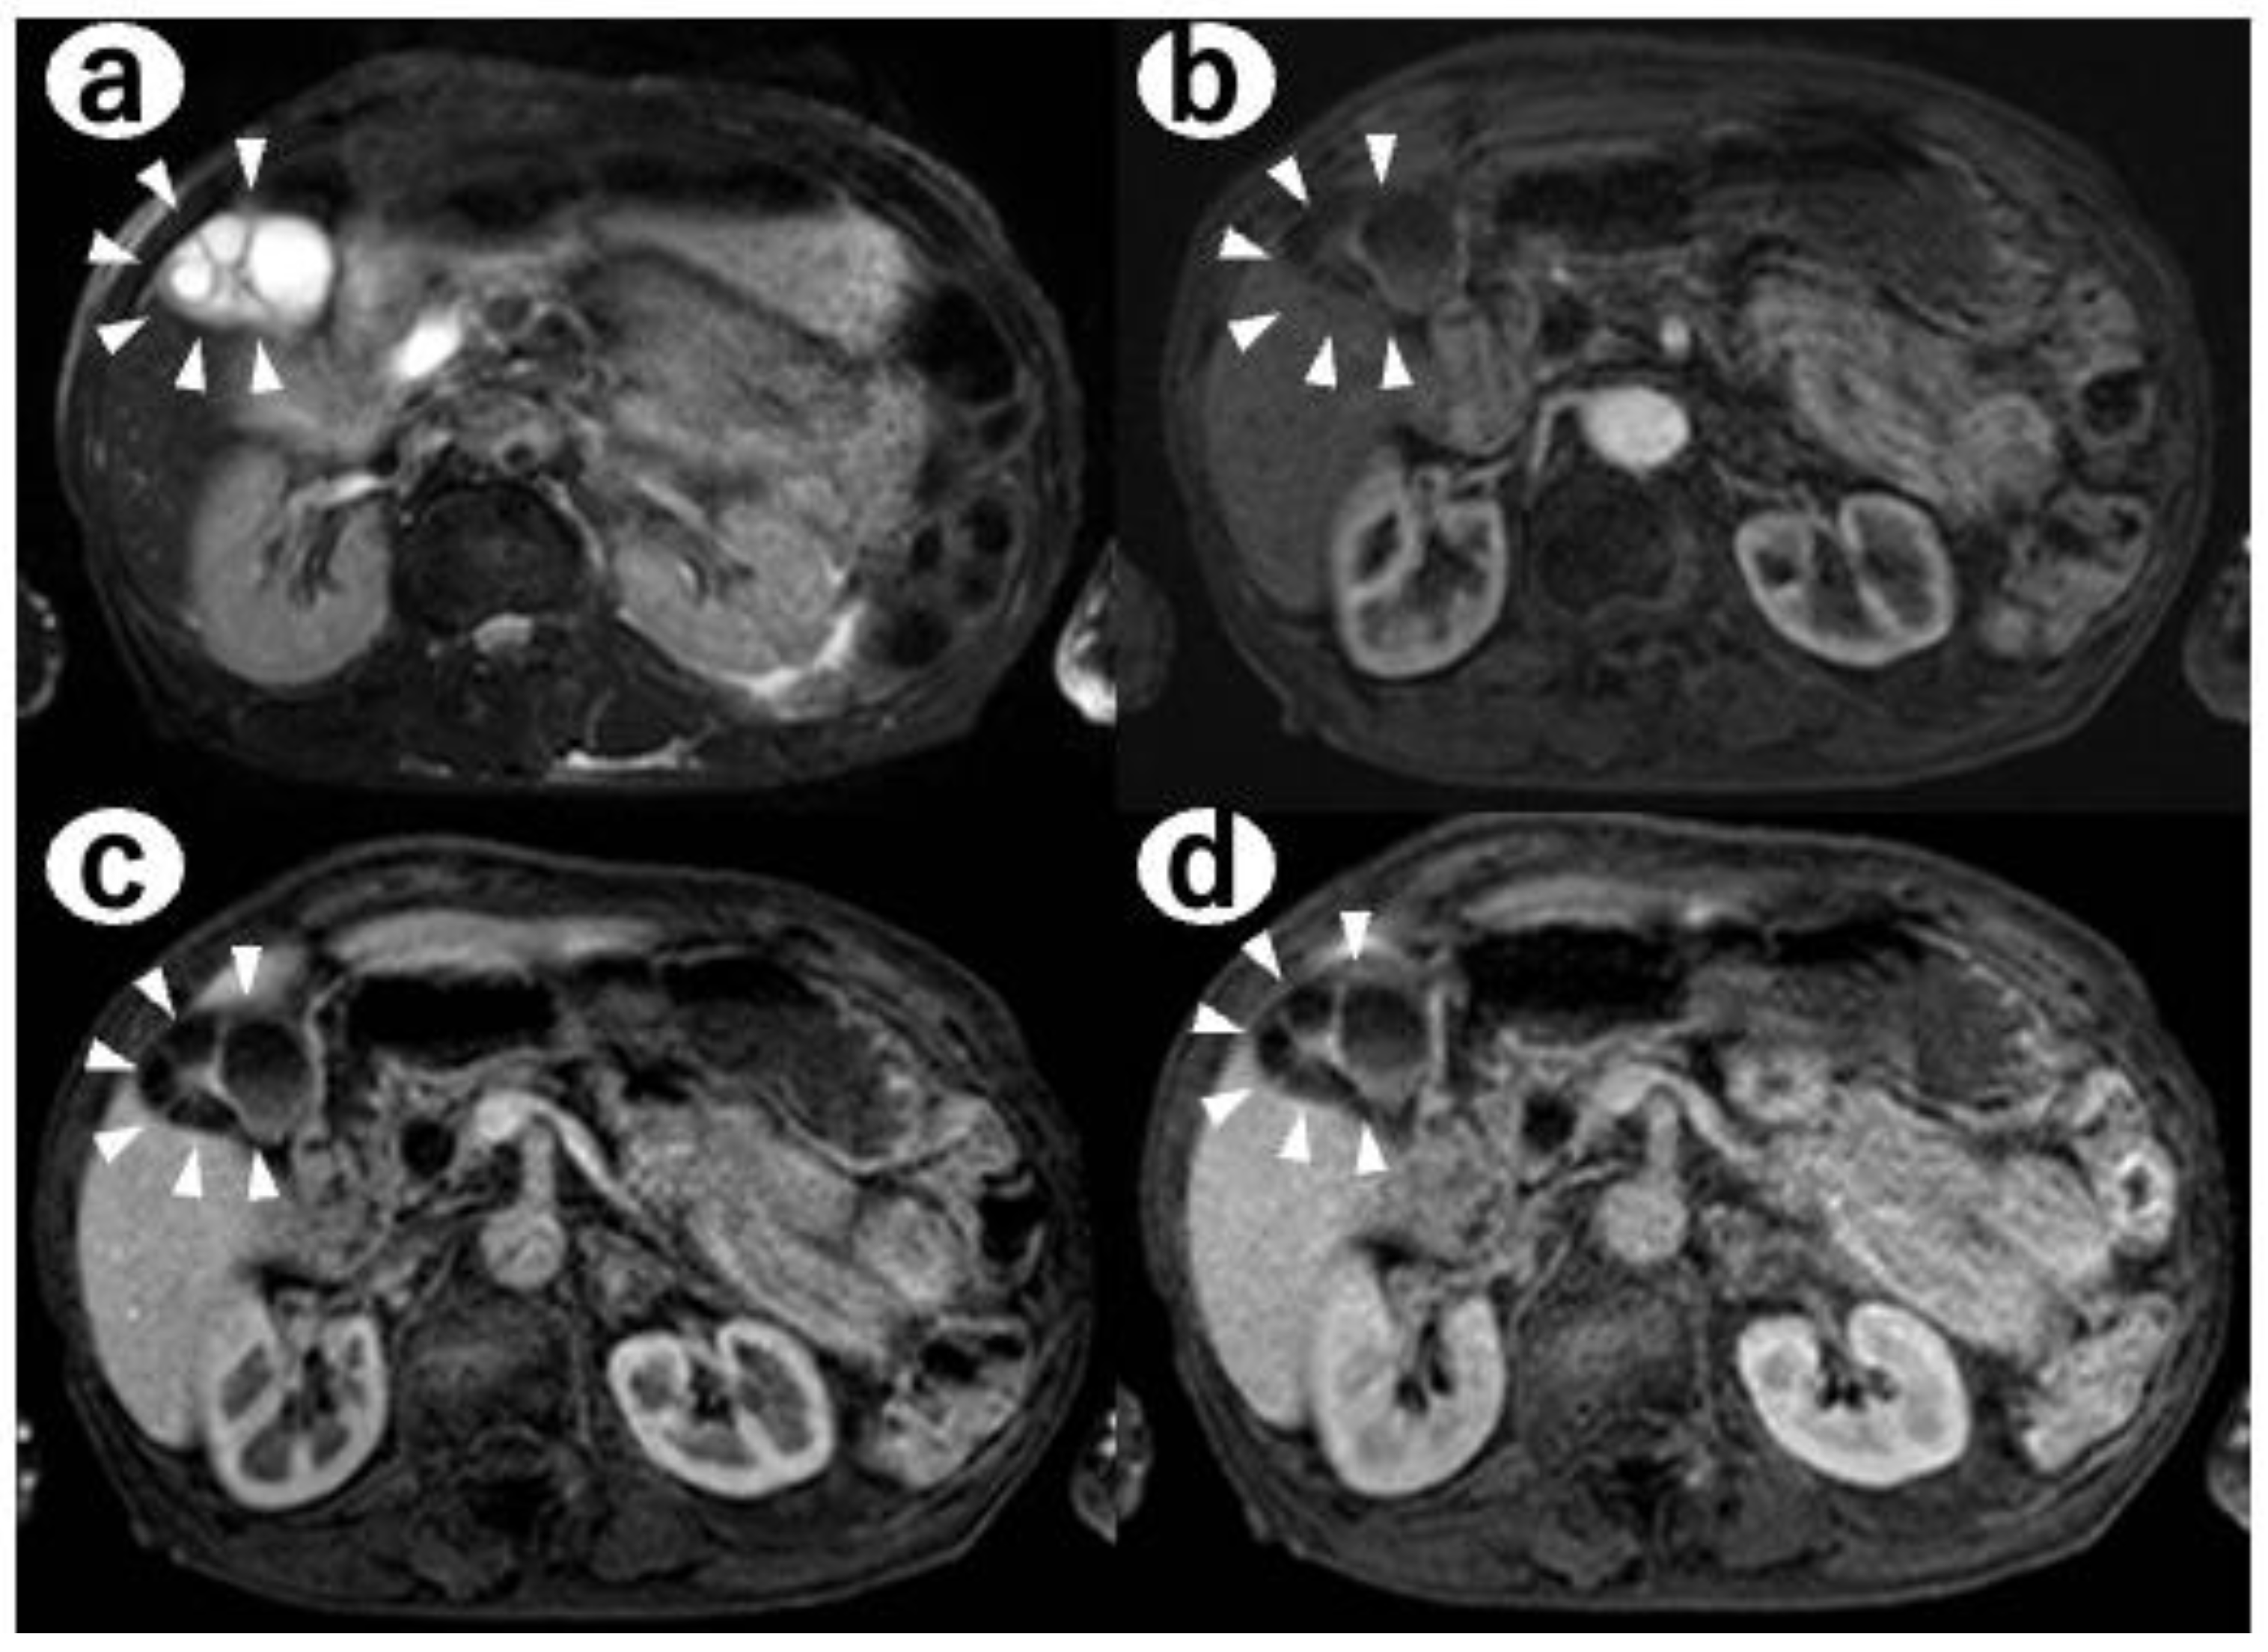

- Contrast-enhanced CT: there were multiple cystic structures at the fundus of the gallbladder and no hyperenhancement of the gallbladder wall or nodules (Figure 2);